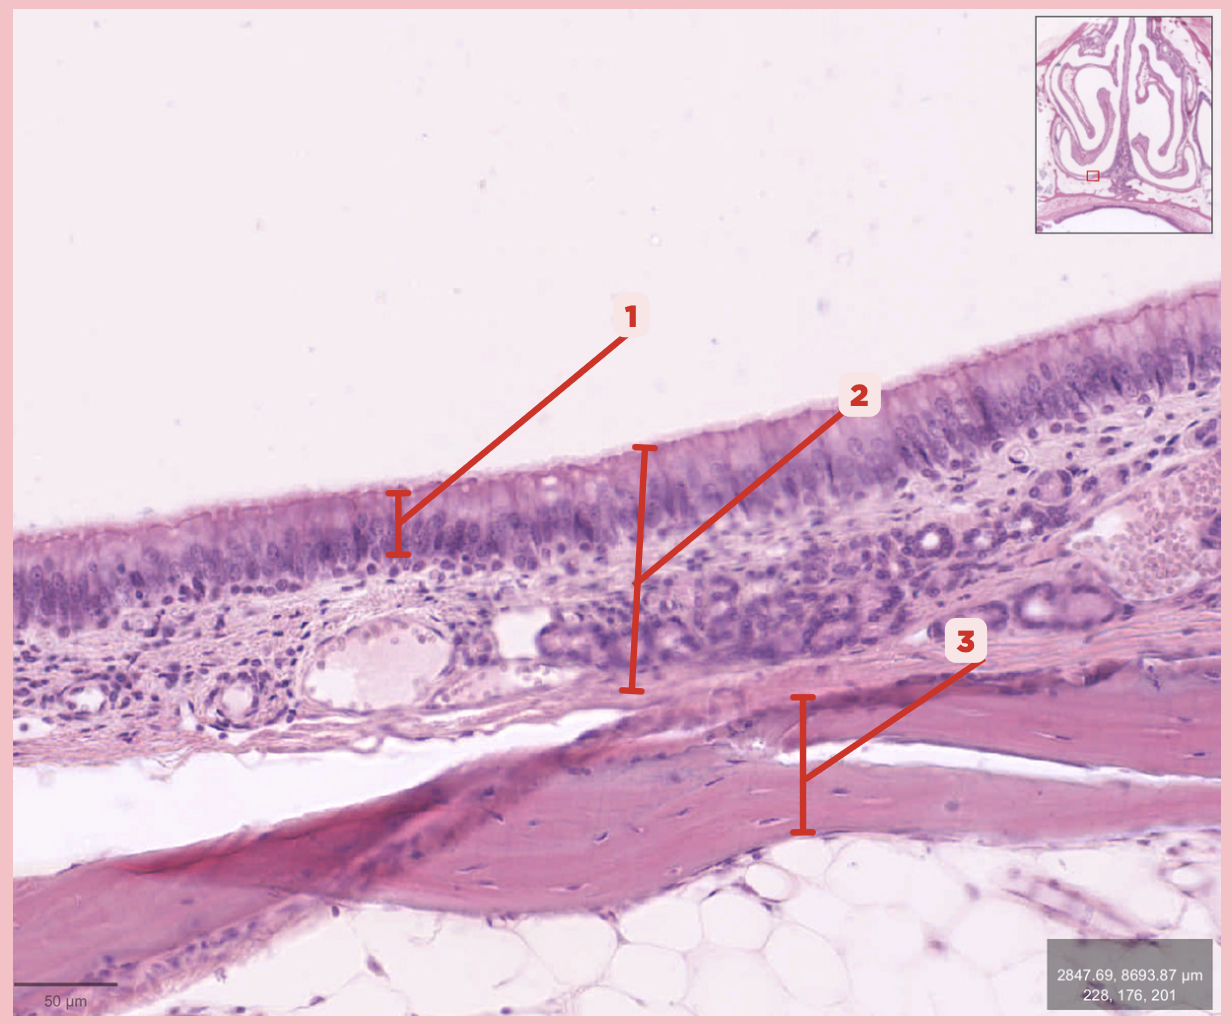

Respiratory Epithelium

Identify the structure labeled as 1.

Lamina Propria

Identify the structure labeled as 2.

Bony spicule

Identify the structure labeled as 3.

Respiratory Epithelium

Identify the structure labeled as 1.

Mucosa

Identify the structure labeled as 2.

Bone

Identify the structure labeled as 3.

Keratinized stratified squamous epithelium

What’s the lining epithelium at #3?

No

Are Glands present at #1?

Lamina Propria

Identify the structure labeled as 1.

Adipocytes

Identify the structure labeled as 2.

Keratinized stratified squamous epithelium

Identify the structure labeled as 3.